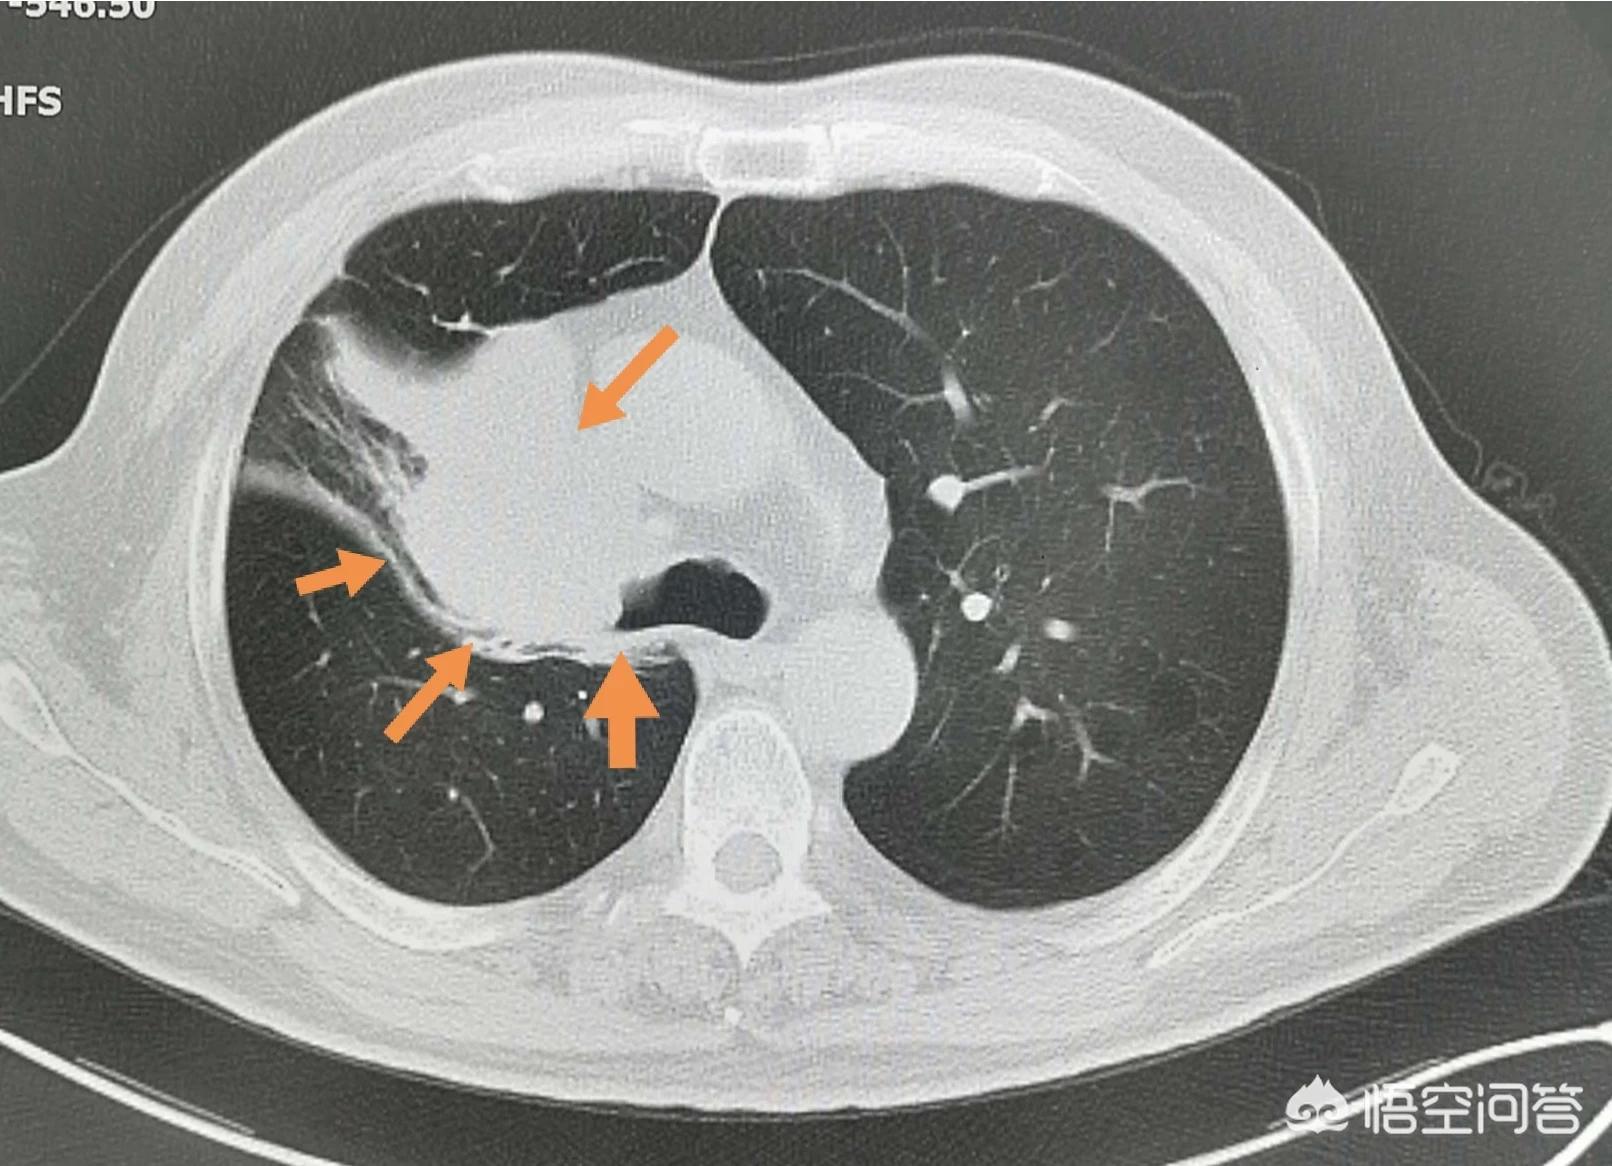

上图,这是一位60岁的男子,抽烟25年,每天一包半,经常咳嗽,去年过完年就开始逐渐加重,主动戒烟一段时间也不见好,一直拖了有三个月才过来检查,结果是中心型肺鳞癌,把气管都快堵住了,肿块太大,治疗很麻烦。

像这位62岁老烟民,抽烟40多年,反反复复的咳嗽,持续两个多月,偶尔有低烧,口服消炎药有一点好转。最近一周加重了,CT发现右侧肺肿块,穿刺确诊为肺鳞癌。

这位病人比较幸运,肿瘤没有发生远处转移,手术快3年了。